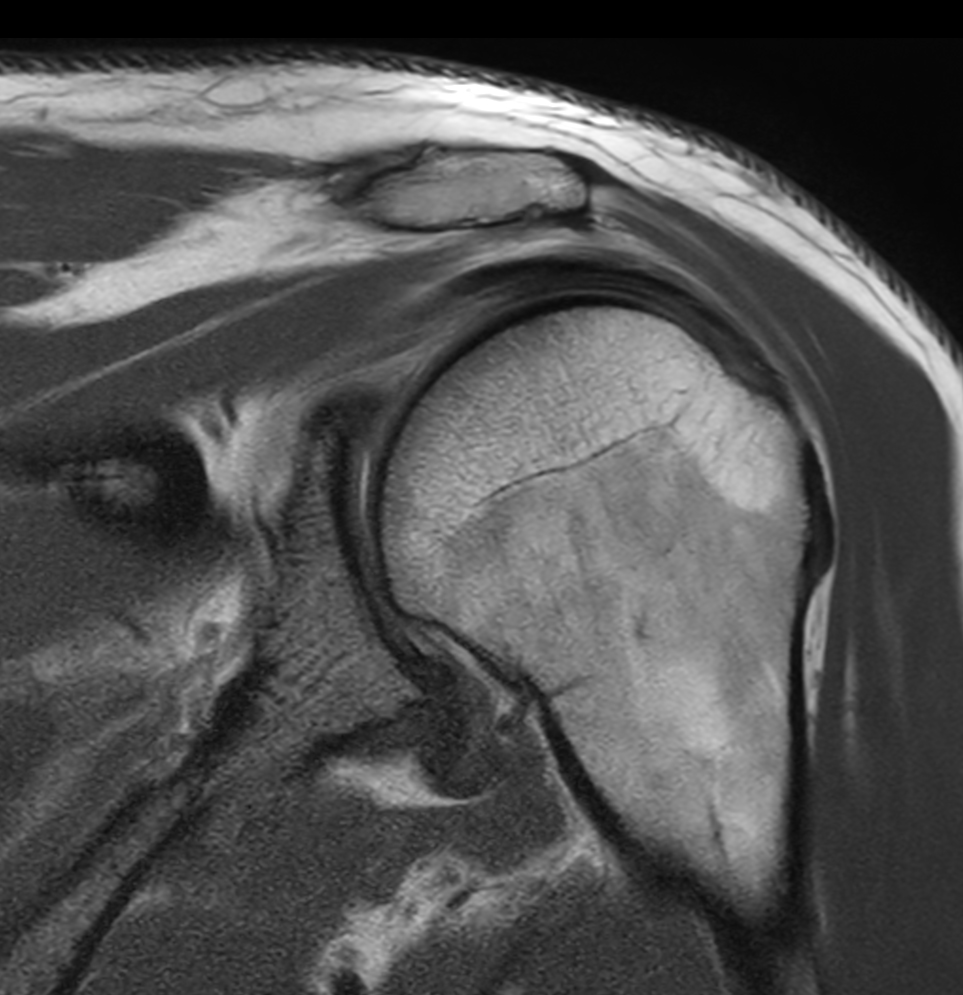

Patient with a shoulder tear

Coronal PDw aTSE